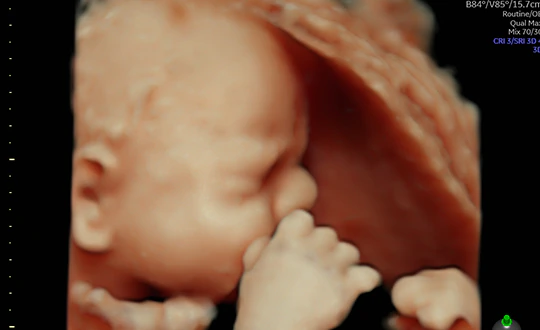

Lo studio del Prof. Susini dispone dell’avanzato sistema ecografico dotato di Intelligenza artificiale completamente integrato che riconosce le 20 visualizzazioni raccomandate dalla International Society of Ultrasound in Obstetrics and Gynecology. Gli strumenti di imaging che sfruttano la potenza dell'intelligenza artificiale consentono di identificare automaticamente ad un livello superiore l'anatomia fetale rispetto a quella visualizzata nelle viste ostetriche standard. Una combinazione di tecniche avanzate di illuminazione e oscuramento della pelle in 3D per visualizzare immagini con chiarezza e profondità senza precedenti e di misurazione della biometria fetale, che consente di allineare e visualizzare correttamente le immagini e le misurazioni consigliate e necessarie per la valutazione del cervello fetale.